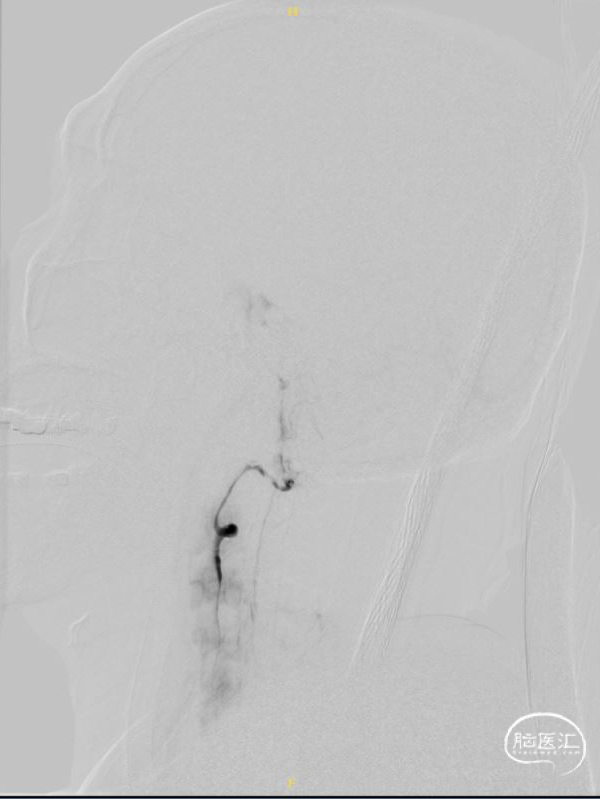

右椎正侧位造影提示:右椎止于小脑下后动脉。

左椎正侧位造影提示:血流缓慢,左椎起始部迂曲,BA下段重度狭窄。

超选左椎行3D旋转造影。